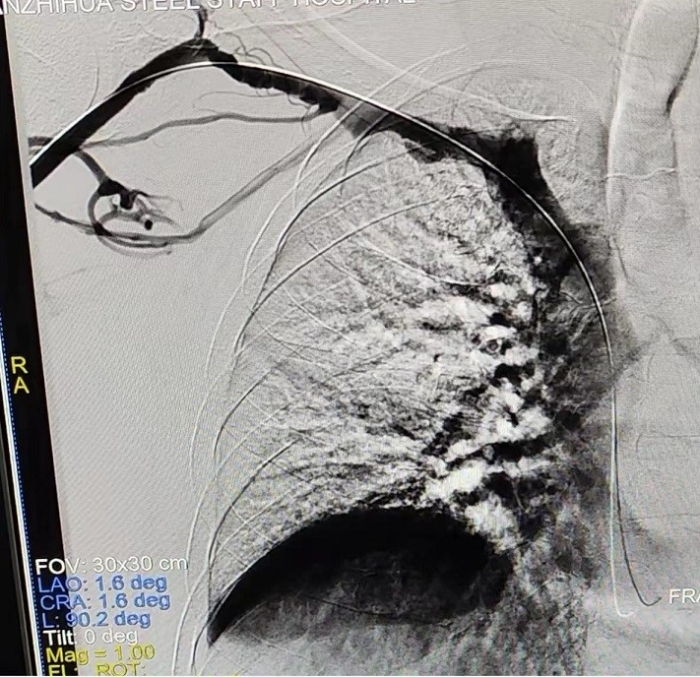

術(shù)后造影顯示:右鎖骨下靜脈狹窄完全打開

手術(shù)中,主刀醫(yī)生唐靜通過DSA順利對人工血管中形成的血栓進(jìn)行了取栓。之后,在中心靜脈造影下,發(fā)現(xiàn)患者中心靜脈外周有2cm的狹窄,尤其是右鎖骨下靜脈得狹窄已經(jīng)嚴(yán)重到幾乎閉塞,針眼大小的縫隙僅能容下導(dǎo)絲通過。經(jīng)過反復(fù)嘗試與不懈努力,終于將導(dǎo)絲置入,并用12 *40mm的球囊擴(kuò)張,右鎖骨下靜脈成功開通,患者透析的通道打開了。術(shù)后,家屬看著消腫的手臂感激萬分,眼淚奪眶而出。